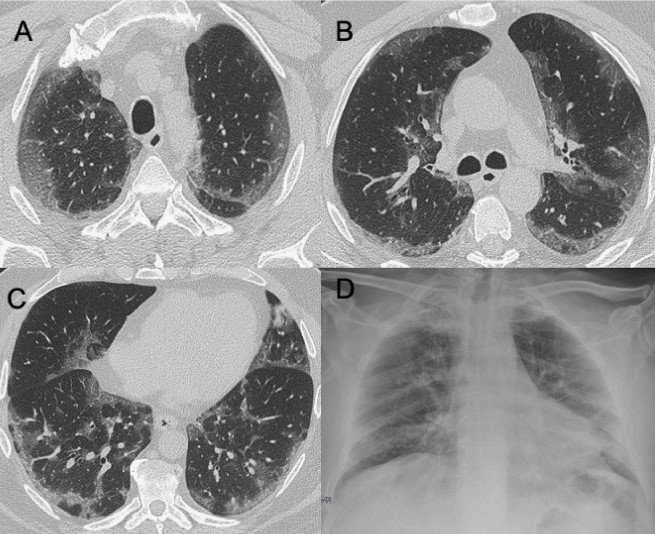

● CT:早期主要為外周、雙側(cè)磨玻璃影(ground-glass opacities,GGO),伴實(shí)變、小葉間隔和小葉內(nèi)間隔增厚,形成“鋪路石征”模式。空氣支氣管征、血管擴(kuò)大、暈輪征和反暈征也有報(bào)告(圖2)。

圖2 COVID-19的HRCT。急性期,雙肺(A)彌漫性GGO,小葉周圍型(B)。圖(C,D)顯示2例亞急性間質(zhì)性肺炎,GGO減少,存在胸膜下局灶性實(shí)變和小葉間/小葉內(nèi)間質(zhì)增厚。